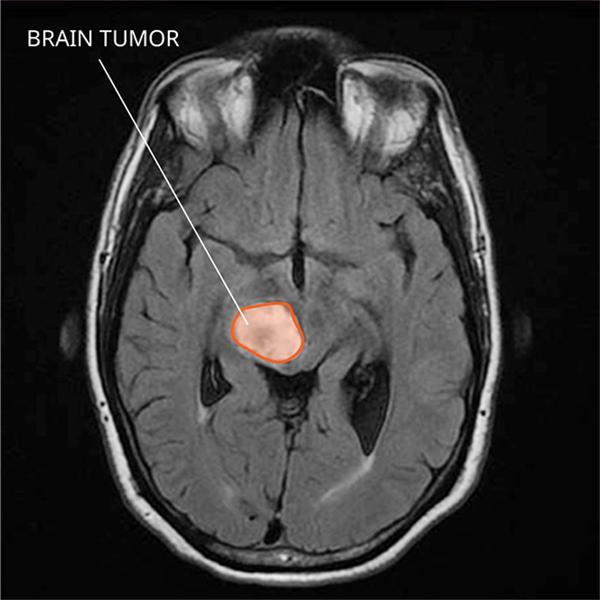

中线胶质瘤

弥漫性中线胶质瘤是什么?

什么是弥漫性中线胶质瘤? 弥漫性中线胶质瘤是一种高...

弥漫中线胶质瘤是什么?

弥漫性中线胶质瘤是什么病? 弥漫性中线胶质瘤是一种...